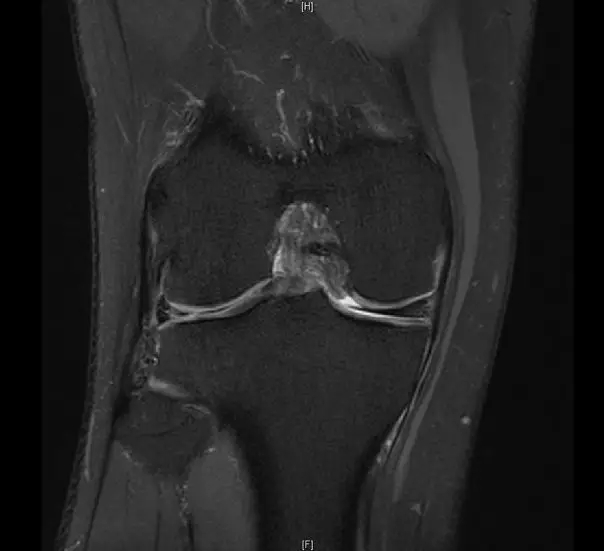

前交叉韧带断裂,外侧半月板后角撕裂

从此片我们可以看到前交叉韧带的上止点高信号,前交叉韧带角度增加,后交叉韧带的夹角增大,从这个层面可以看到外侧半月板边缘不清楚不完整质地不均一,混杂有高信号的改变,并且内部有一些裂隙,从这个层面我们可以看到前交叉韧带的下止点相对比较完整,而这个层面上止点信号异常,韧带松弛并且有大量的渗出病变,缺乏张力。这个层面也可以看到髁间窝这个部位凸起,看不到应有的上止点信号。所以这个病例我们需要考虑前交叉韧带断裂,外侧半月板后角撕裂。